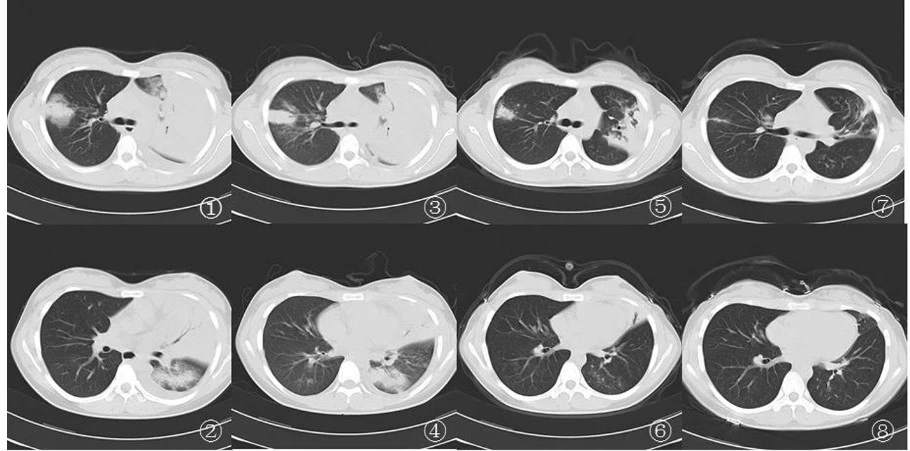

五、军团菌肺炎影像

军团菌肺炎胸部影像相对特异性的表现是磨玻璃影中混杂着边缘相对清晰的实变影。虽然临床症状改善,影像学在短时间内仍有进展(1周内),或肺部浸润影几周甚至几个月后才完全吸收也是军团菌肺炎的影像学特点。

注:①②患者入院第1天胸部CT示双肺多发斑片样渗出影,左上肺实变,内可见支气管充气征,伴有左侧少量胸腔积液;③④治疗1周后右上叶渗出影略有减小,左侧胸腔积液减少(胸穿术后);⑤⑥治疗6周后双肺渗出影明显吸收好转;⑦⑧双肺渗出影基本吸收,左上肺叶遗留纤维索条影和坏死物质排出后形成的空腔。